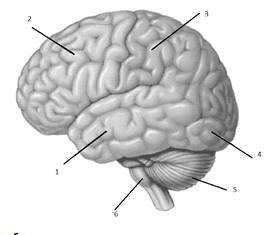

Анатомические снимки верхнелатеральной поверхности головного мозга